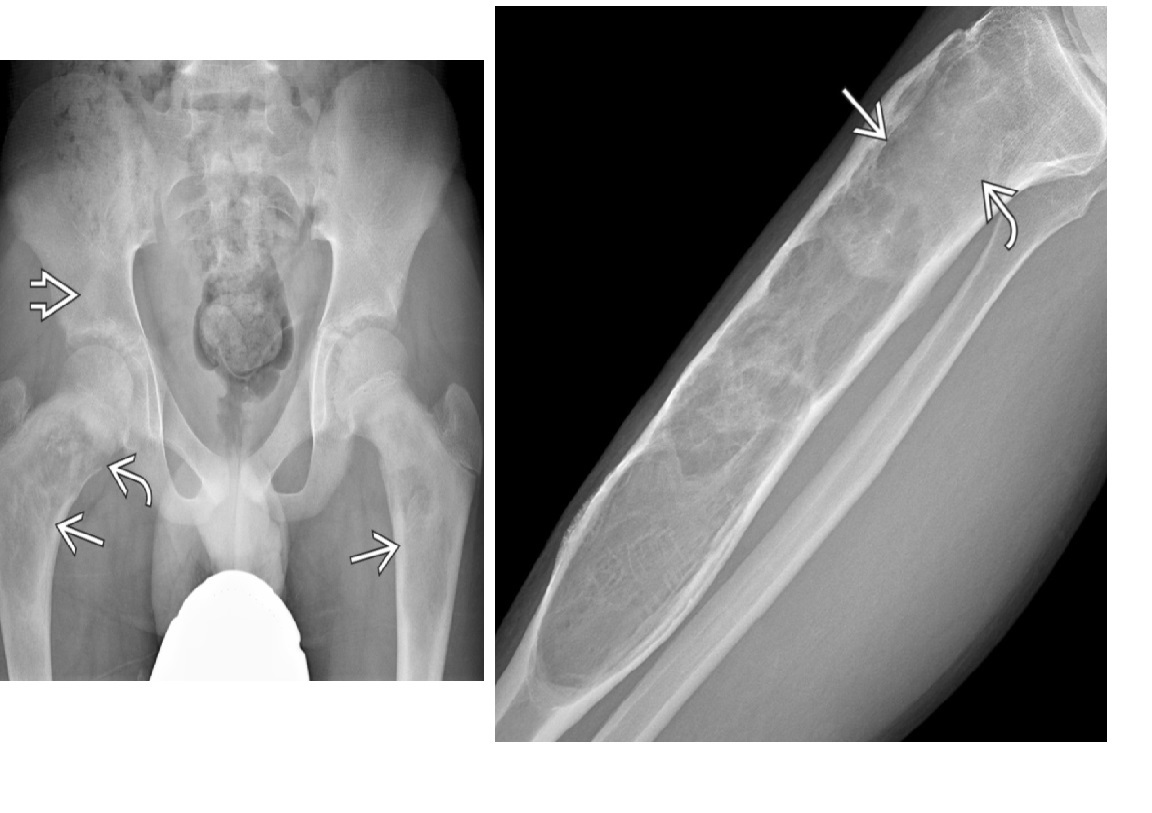

Chondrosarcoma

May be cecondary to

- Osteochondromas

- enchondromas

Chondrosarcomas occur in the pelvis, femur, humerus.

Skull base, TMJ

DDX

-Most well differentiated, low grade = ‘low grade chondroid lesion’ , cant differentate from enchondroma

-Bone infarct

MRI

Lobular growth

High 2 signal/STIR, low T1

ring and arcs/chondroid matrix islands on CT

Soft tissue extension

**endosteal scalloping. **

if no mineralized matrix/rings and arcs = aggressive/high grade

How to tell chondrosarcoma from enchondroma ?

* Pathological fracture occurring with minimal trauma

* Multilayered or spiculate periosteal reaction

* Permeative or moth-eaten osteolysis

* Cortical destruction

* A soft tissue mass

Endosteal scalloping more than 2/3 cortex